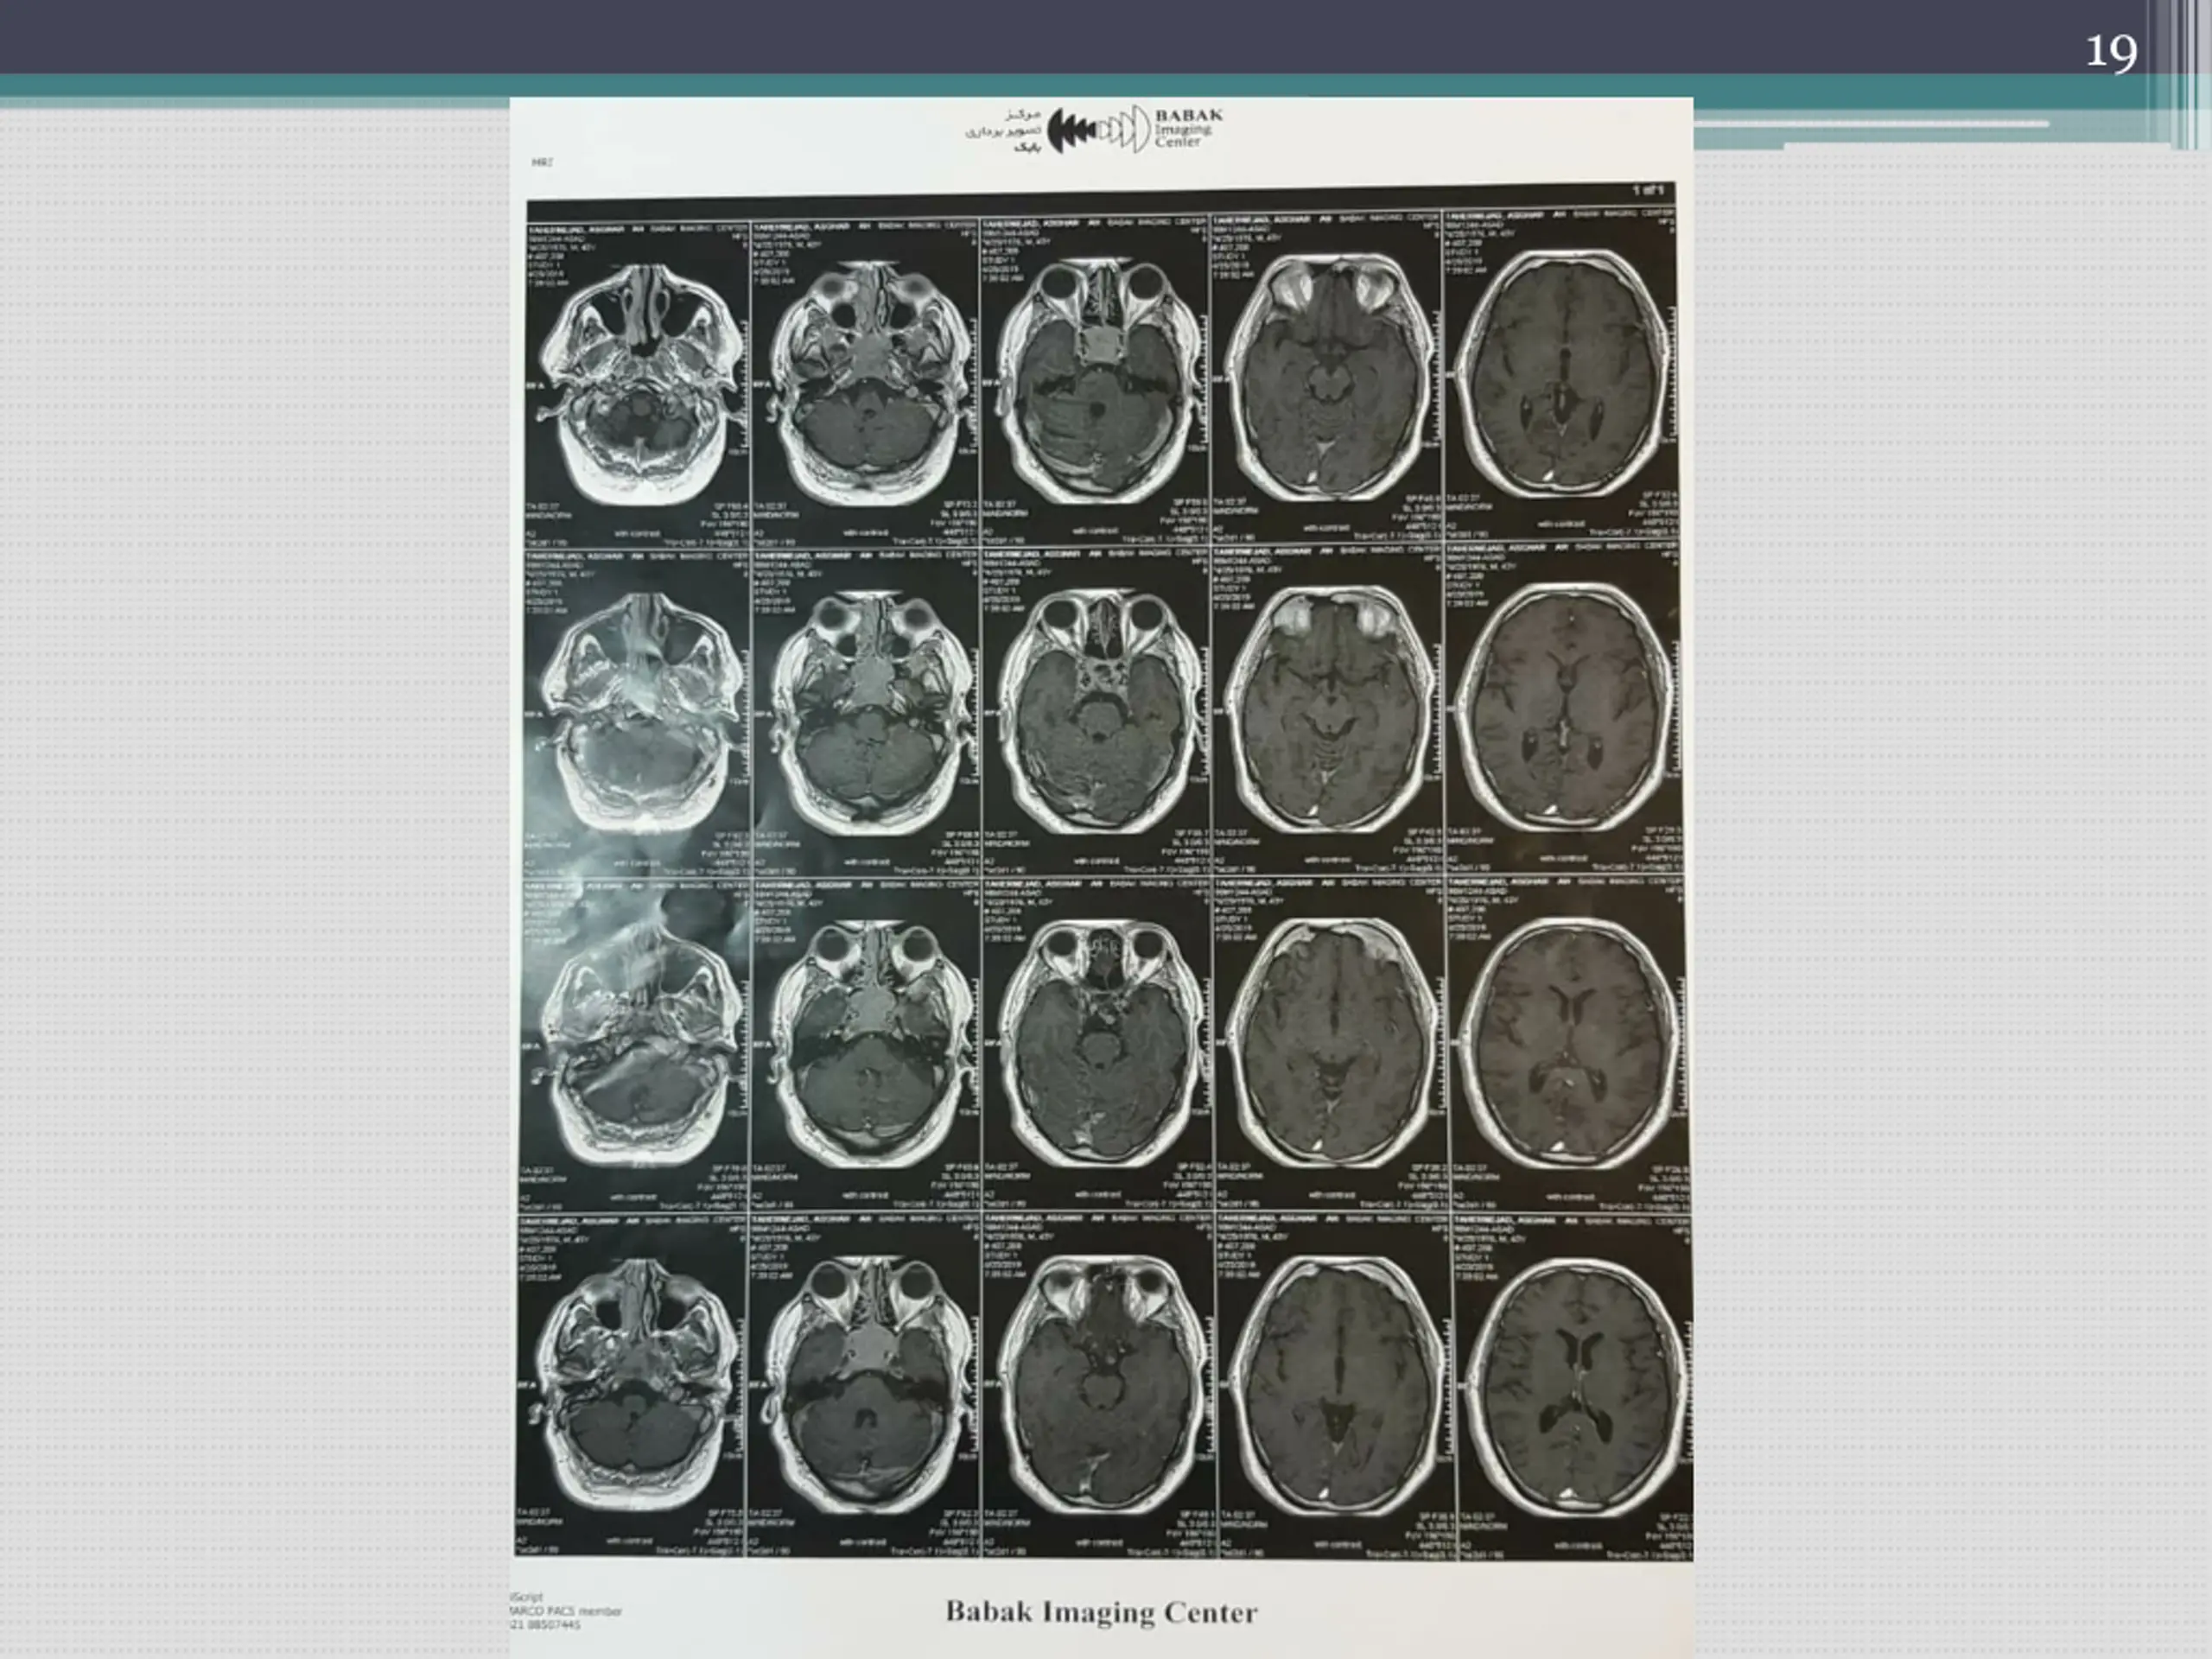

9 in December 2019(Farvardin 98), referred to a physician in Tabriz because of no improvement in symptoms. MRI was taken Laboratory investigation was done.

11 Report : 7/1/98 Iso signal SOL with homogenous enhancement and snowman appearance, measuring about 40*38 mm in sella, causing elevation and compression of optic chiasma and depression of floor of sella. Enhancement of bilateral cavernous sinuses by the mass. Pituitary macroadenoma is the most probable diagnosis. No ischemic sign.